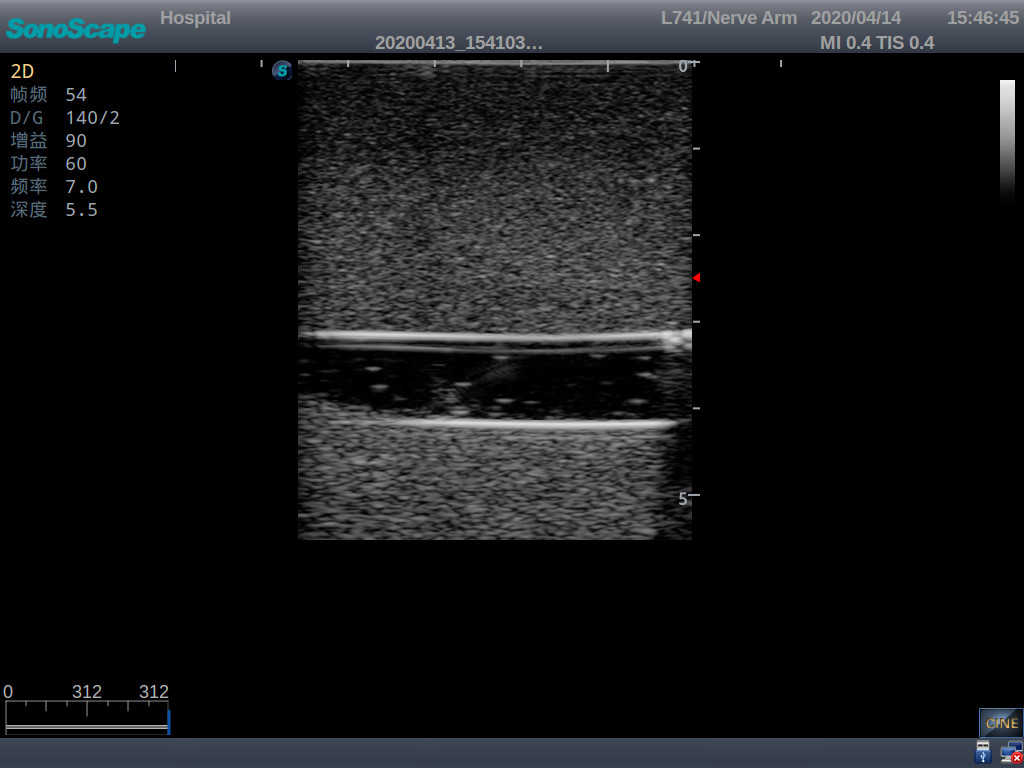

3)   Clear and real images of the tissues and organs (basilic vein and superior vena cava)

6)   Detect whether the catheter is properly placed